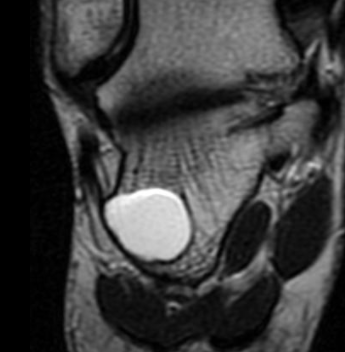

IRM

- Signal Kystique HyperT2 HypoT1

- Possible niveau si hémorragie

Localisation Calcanéenne Typique